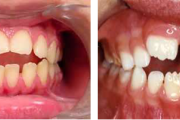

Turritavad ülemised lõikehambad.

Ülemise hambakaare kitsenemine ehk tagumiste hammaste risthambumus.

Ruumipuudus eesmiste hammaste osas